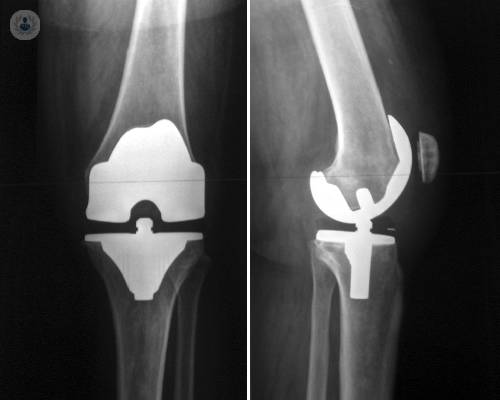

• protesis-de-rodilla-reemplazo-de-rodilla

Redacción de Top Doctors

05/10/2016

Cuándo es necesaria una prótesis de rodilla y garantías que ofrece al paciente

La cirugía de reemplazo de rodilla implica la sustitución de los tejidos dañados por una articulación artificial o prótesis de rodilla. El Dr. Giménez, especialista en Traumatología, explica cuándo debe realizarse.